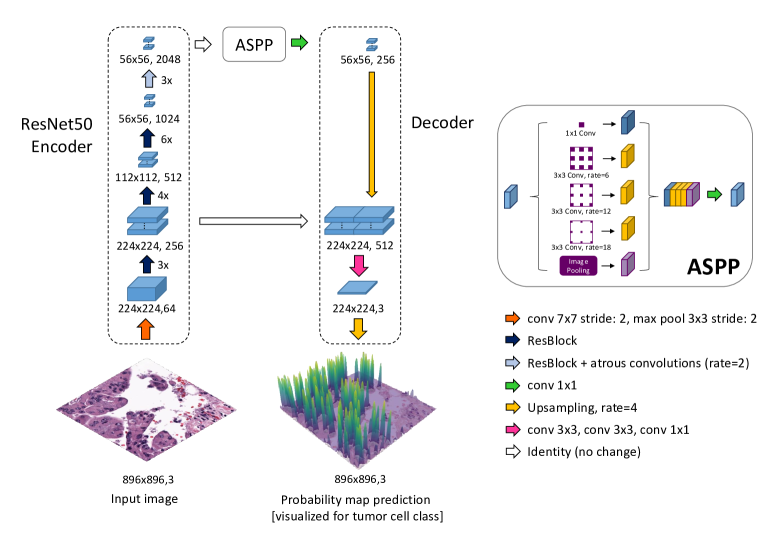

Building on [11] we utilize a DeepLabv3+ segmentation model [4] with a ResNet50 [6] encoder pretrained on ImageNet111Pytorch default pretrained weights: https://pytorch.org/vision/stable/models/generated/torchvision.models.resnet50.html#torchvision.models.ResNet50_Weights, last accessed 24.11.2023 as shown in Figure 1. The last ResNet50 convolutional block utilizes atrous convolutions with a rate of 2, to enable downsampling while preserving the input feature dimension. This is followed by an Atrous Spatial Pyramid Pooling (ASPP) block [3] and a decoder. The ASPP block extracts high-level-features at different downsampling rates to account for differing object scales. The decoder consists of two upsampling steps, connected by three convolutional layers which combine low-level features from the second ResNet50 layer with high-level features from the upsampled ASPP output. We utilize the same model architecture for cell detection and tissue segmentation.